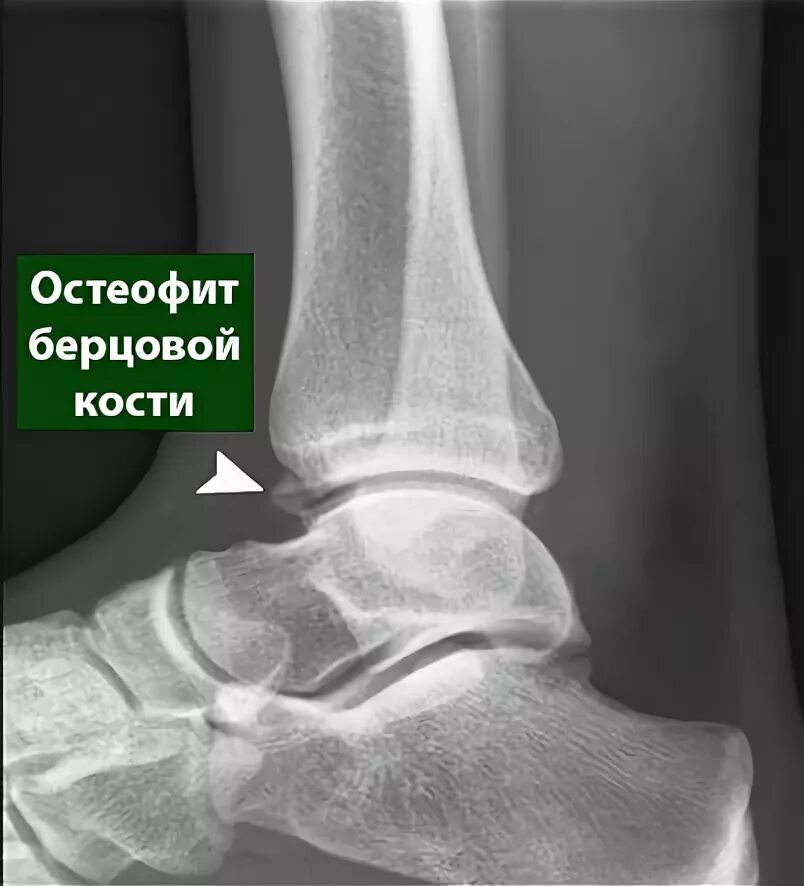

Лечение остеофитов сустав